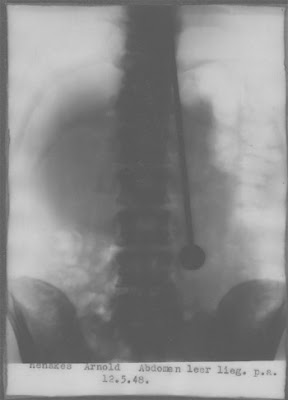

- Mirin Dajo เป็นฉายานามที่มีความหมายว่า "มหัศจรรย์" โดยเขามีชื่อจริงว่า Arnold Gerrit Henskes เป็นชาวดัทช์(Dutch) เกิดเมื่อ 6 สิงหาคม 1912

- ในปี 1948 เขาอ้างว่าได้ยินเสียงบอกให้เขากิน เข็มเหล็ก และเราก็กินมันลงไปจริงเมื่อวันที่ 11 พฤษภาคม 1948 ควรนี้เขาต้องถูกผ่าตัดเอาเข็มออกจากพุงในวันที่ 13 พฤษภาคม 1948 และตายลงในวันที่ 28 พฤษภาคม 1948 เมื่อทำการผ่าพิสูจน์แพทย์พบว่าเขาเสียชีวิตจากอาการ หลอดเลือดแดงเอออร์ฉีกขาด(Aortic rupture)